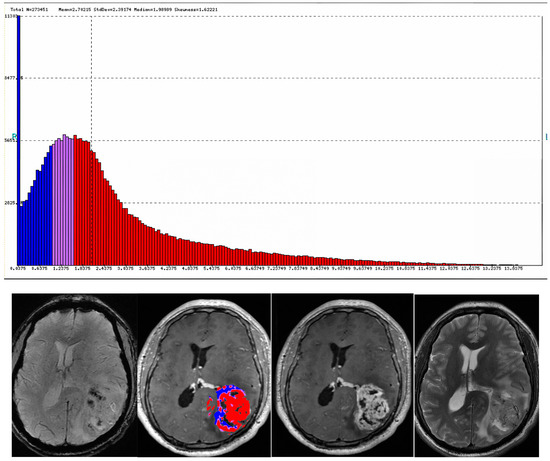

- Lohmann, P.; Kocher, M.; Ceccon, G.; Bauer, E.K.; Stoffels, G.; Viswanathan, S.; Ruge, M.I.; Neumaier, B.; Shah, N.J.; Fink, G.R.; et al. Combined FET PET/MRI radiomics differentiates radiation injury from recurrent brain metastasis. NeuroImage Clin. 2018, 20, 537–542. [Google Scholar] [CrossRef] [PubMed]

- Müller, M.; Winz, O.; Gutsche, R.; Leijenaar, R.T.H.; Kocher, M.; Lerche, C.; Filss, C.P.; Stoffels, G.; Steidl, E.; Hattingen, E.; et al. Static FET PET radiomics for the differentiation of treatment-related changes from glioma progression. J. Neuro-Oncol. 2022, 159, 519–529. [Google Scholar] [CrossRef] [PubMed]